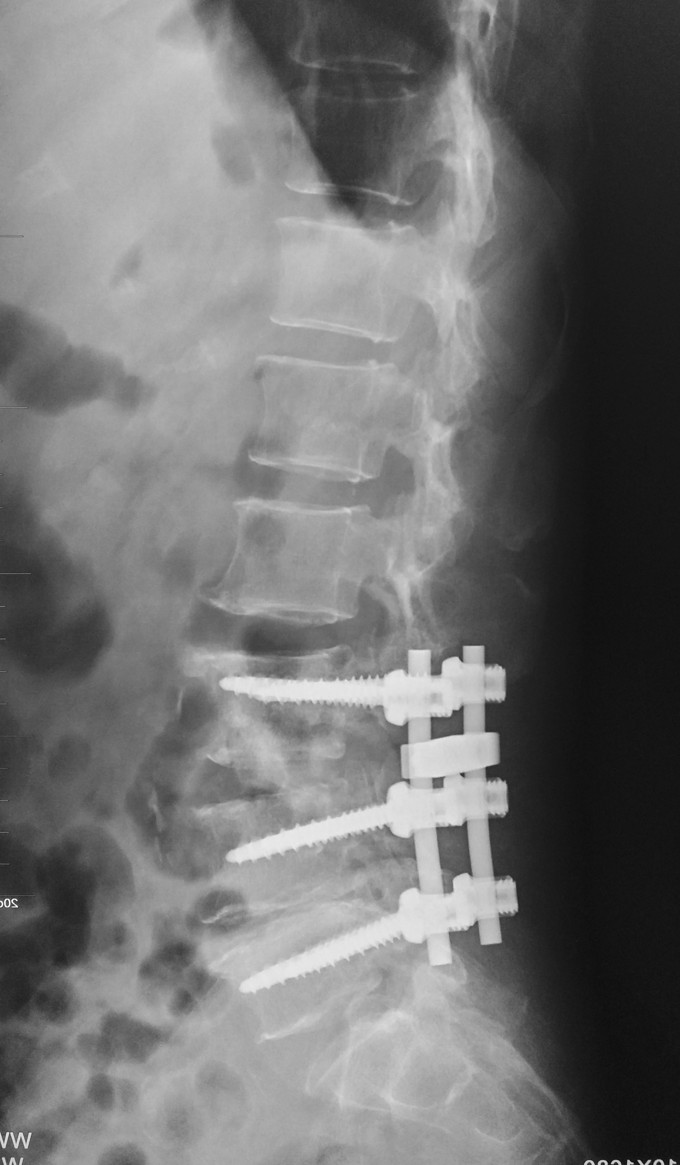

1.腰3-4结核 2.腰4-5椎管狭窄 因术前血沉比较高,所以予以HREZS抗痨治疗2周,血沉至44mm/h,患者一般情况较前好转。安排手术治疗:后路腰3-4椎间病灶清除椎板植骨+腰4-5减压植骨内固定融合术。

此患者腰椎结核伴有相邻节段椎管狭窄,所以兼有两者的症状。对于此病例我们考虑因患者椎体前方脓肿不明显,所以考虑一起行后方椎间隙病灶清除,植入自体椎板骨融合内固定,同时进行腰4-5后路减压内固定融合术。 不知大家对结核的病人一般是通过何种方式进行病灶清除的?选择原则是什么?